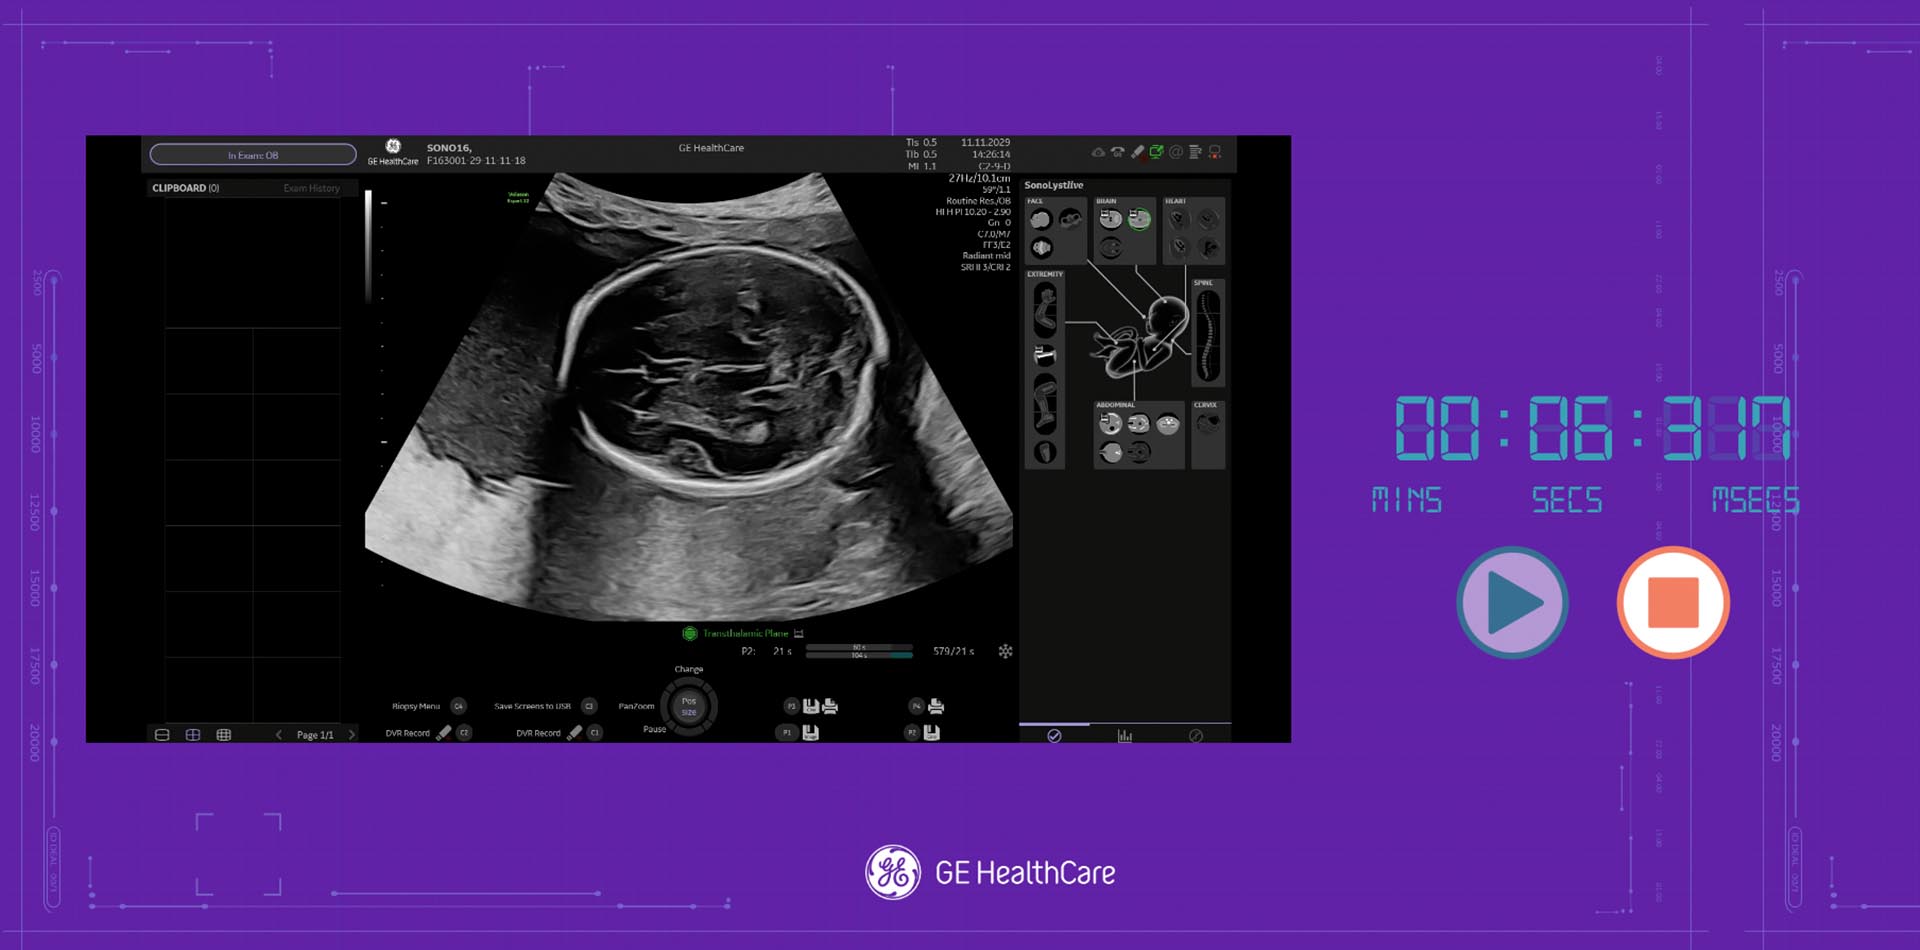

Using a combination of strategic insight and a creative ideation process, the team at TrunkBBI developed multiple game ideas, from a simple quiz to a more complex ‘Beat the AI’ concept, allowing sonographers to test their skills against a pre-programmed scan in real-time. The intent was for this to showcase the incredible power of GE HealthCare’s machine AI capability, and prove to our audience how it could help reduce scanning time in a busy role.

The concepts worked on multiple levels – continuing with GE HealthCare’s goal of highlighting new ultrasound machine updates, and as a way to engage more fully with BMUS attendees and collect information for follow-up.